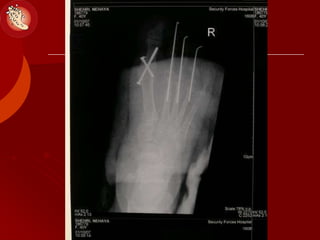

Patterns of Bone &Joint Destruction

(Ulcers & Charcot)

 Forefoot: MTP, IP

 Lisfranc:

 Chopart: TN-, CC- joint

 Ankle joint

 Calcaneus